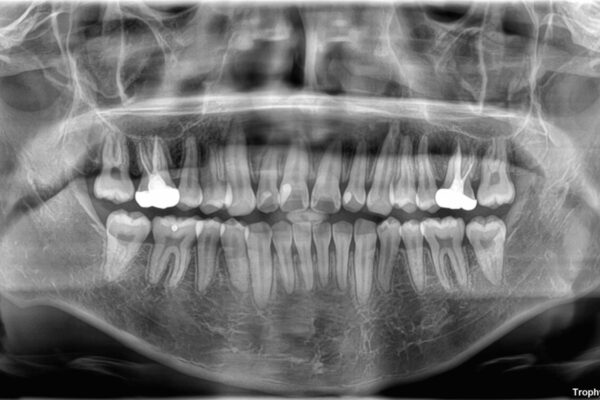

治療後

• 1年でここまで変わる!歯列のがたつきと正中のズレを改善した矯正治療(メタルブラケット×MARPE) 治療後画像

適切な診断と装置の選択により、1年という短期間でここまで改善できます。

見た目の美しさだけでなく、将来のむし歯や歯周病リスクを減らすことにもつながる治療です。